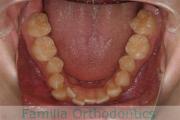

上顎

下顎

前歯の関係など

右側

正面

左側

歯並びを治したいということで来院されました。下あごがやや右側に偏位して後退している、上顎前突(出っ歯)でした。上下左右から小臼歯を抜歯して、歯科矯正用アンカースクリューを併用したマルチブラケット法にて治療を行いました。約2年、24回の来院をしていただきました。

下顎の後退はいびきなどの上部気道の障害が出やすいと考えられます。